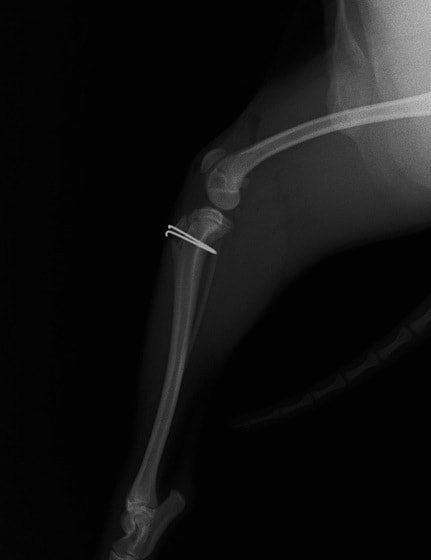

■ 症例20 ポメラニアン 8ヶ月 1.8kg

左右膝蓋骨脱臼 グレードⅢ

2ヶ月前から間欠的跛行が認められ、両膝の膝蓋骨脱臼整復術を行った。

手技は縫工筋及び内側広筋の解放、脛骨粗面の外側転位、滑車ブロック形造溝術、内外側関節包の縫縮を選択し実施した。

右側の膝蓋骨脱臼は上記手技で整復されたものの、左側はそれのみでは膝蓋骨が浮く様子が認められた。その為、PDS縫合糸にて膝蓋靱帯を1糸のみ縫合し、靱帯の縫縮を行った。

膝蓋骨脱臼は膝関節における膝蓋骨の内外側の脱臼と定義されるが、時として単純な内外の脱臼ではなく、膝蓋骨が大きく前方に浮き上がるように脱臼する場合がある。特にトイプードルやポメラニアンといった犬種に多く認められる。

内側脱臼に加えて前方への浮き上がりを矯正する為に、従来より脛骨粗面転移により膝蓋靭帯を外方と下方に引っ張り、固定する方法を選択する。膝蓋骨の前方への浮き上がりが軽度の場合は、従来法ではなく関節包の縫縮で対応していた。しかし、一部の症例で膝蓋骨の動きが悪くなり伸展機構が円滑に機能せずロボット様歩行になるケースがあった。

その為、膝蓋靭帯自体を縫縮する方法を採用した。この方法により、膝関節の伸展機構を妨げず膝蓋骨の軽度の浮きを矯正することが可能となった。

本症例の経過は良好である